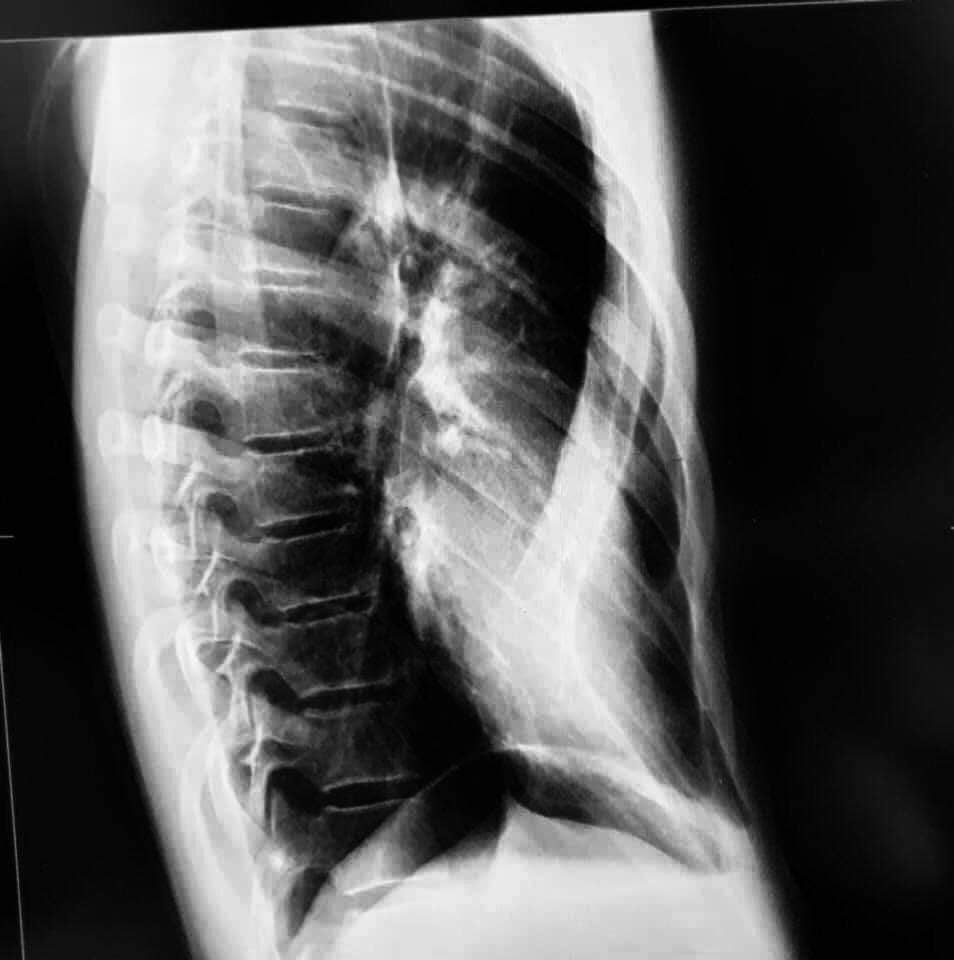

Цээжний хонхойх гажиг засах хос титанан суулгац тавих дурангийн мэс засал нь өвчүүний араар болон өмнө талаар махир металл суулгац байрлуулах замаар цээжний хэлбэрийг засдаг маш жижиг хүрцийн мэс заслын орчин үеийн арга юм.

Цээж өвчүүний хонхойх гажиг болон цээжний хэлбэрийн өөрчлөлтөөс болж өвчтөнд зүрх, уушгины үйл ажиллагааны өөрчлөлт, уушги, зүрхний үйл ажиллагаа хэвийн боловч амьдралын чанарт сөргөөр нөлөөлж буй тохиолдол болон цээжний хонхорхой байдал нь сэтгэл зүйн байдал, нийгмийн харилцаанд сөргөөр нөлөөлж буй үед эмчилгээ хийлгэхийг зөвлөдөг.